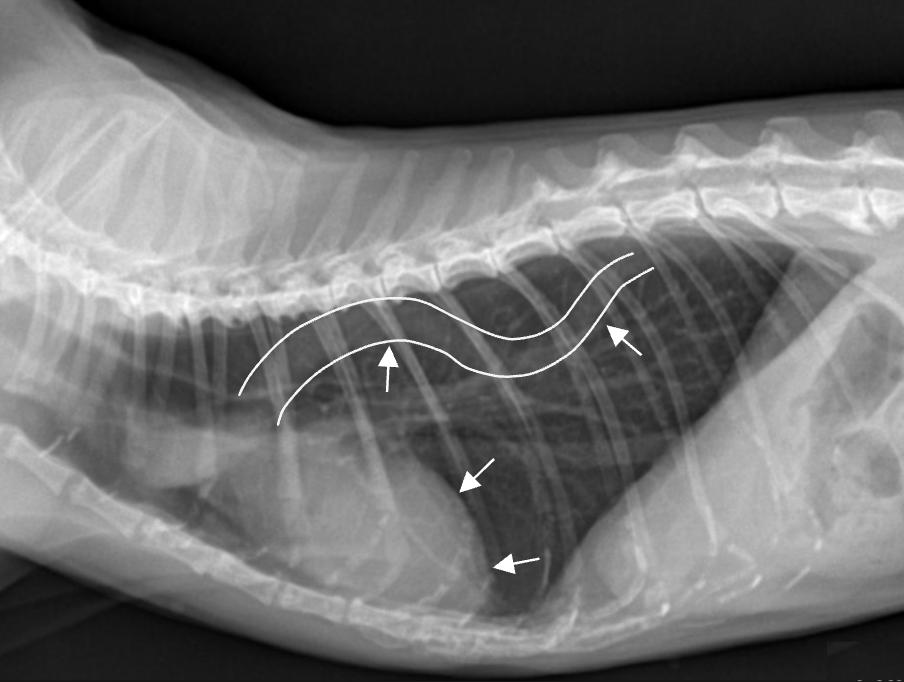

==Knob sign== ![]() - 나이 많은 고양이에서 대동맥이 구불해지고, 심장이 누움. |